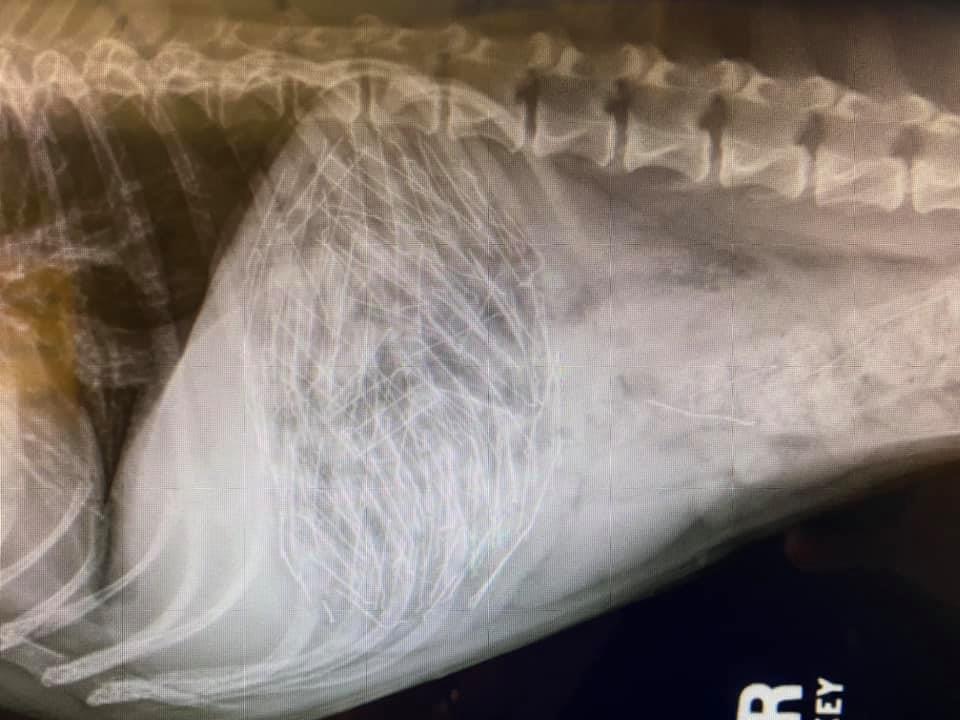

2021 They Ate What?! X-ray Contest winnersThey Ate This: Check out the winner, runners-up, and honorable mentions October 4, 2021 < Previous Entry VOTE NOW! Next Entry > Pages: 1 2 3 4 5 6 7 8 9 10 11 12 13 14